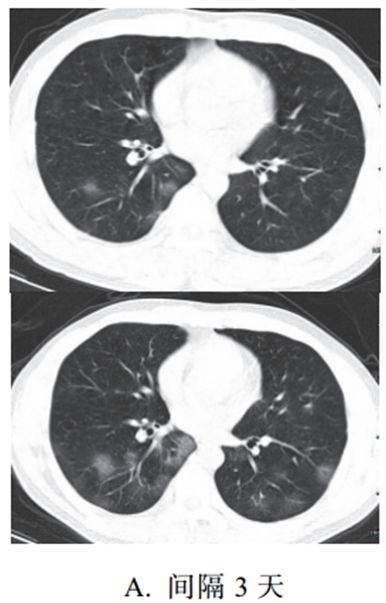

二、进展期征象

新冠肺炎大多数病例进展迅速,复查 CT 影像发生明显变化

表现为病灶数目明显增多,范围明显扩大,密度增高,病灶分布由外周向中央推进

根据既往 SARS 病理学机制,提示为肺泡腔内聚集大量细胞渗出液、间质内血管扩张渗出;肺泡连通起来形成融合态势(图 2-11)